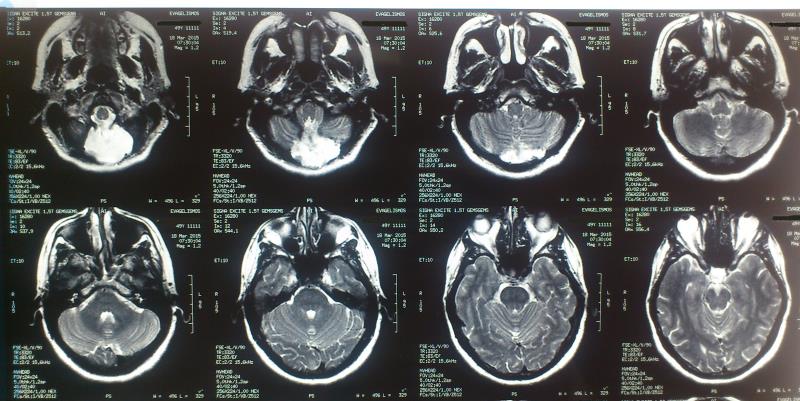

Ασθενής  γυναίκα 49 ετών προσήλθε λόγω υπινιακής κεφαλαλγίας εκλυόμενης και επιδεινούμενης  κατά την επίκυψη και  την άρση βάρους  ( Valsalva maneuvers ) με συνοδό αίσθημα αιμωδιών  άνω και κάτω άκρων. Ο προεγχειρητικός έλεγχος με μαγνητική τομογραφία  του κρανιοσπονδυλικού άξονα ανέδειξε εικόνα συμβατή με Chiari τύπου I : κατάσπαση των παρεγκεφαλιδικών αμυγδαλών 8 mm με κατάληψη- συμφόρηση του ινιακού τρήματος και συνοδό συριγγομυελία καθ’ όλο το μήκος του αυχενοθωρακικου μυελού. Η ασθενής υποβλήθηκε σε υπινιακή κρανιοτομία, αφαίρεση του οπίσθιου τόξου του άτλαντα (Α1) και εκτομή των παρεγκεφαλιδικών αμυγδαλών αποκαθιστώντας την υδροδυναμική του εγκεφαλονωτιαίου υγρού. Πραγματοποιήθηκε πλαστική σκληράς μήνιγγος και δεν επανατοποθετήθηκε ο οστικός κρημνός. Η ασθενής μετεγχειρητικά παρουσίασε  πλήρη ύφεση της κεφαλαλγίας και σταδιακή αποκατάσταση των αιμωδιών. Ο μετεγχειρητικός απεικονιστικός έλεγχος ανέδειξε την αποσυμπίεση στο επίπεδο της κρανιοσπονδυλικής συμβολής και σαφή μείωση των διαστάσεων της συριγγομυελίας.

Μετεγχειρητικός απεικονιστικός έλεγχος